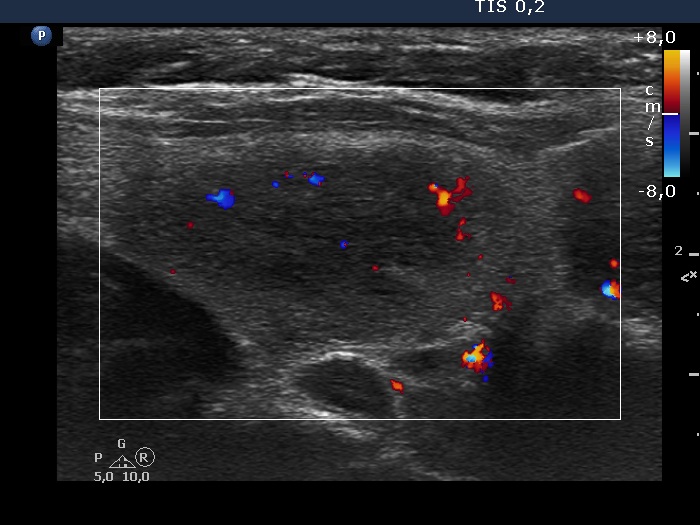

Lower part of the left lobe, longitudinal scan, color Doppler mode. The vascularization in this section is average.